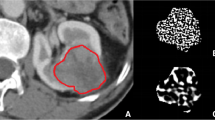

Images obtained in the unenhanced, late arterial, venous, and delayed phases were used for the texture analysis. For each patient, a volume of interest (VOI) of the whole lesion for each phase was selected by means of manual segmentation (Fig. 1) by one radiologist with 15 years of experience in adrenal imaging (C.M.). The feature extraction was carried out using the LIFEx software [16]. Both first-order and second-order features were analyzed. First-order features are extracted evaluating the mean, skewness, and kurtosis of the distribution of Hounsfield Units (HU) of the voxels in the VOI, as well as geometrical features of the lesions such as compacity or sphericity of the VOI. Second-order features are derived from matrixes, calculating, for each voxel in pair with the adjacent ones, indices such as homogeneity, contrast, correlation, entropy, and dissimilarity for the grey-level co-occurrence matrix (GLCM) [16, 17]. This approach was purely explorative and not prognostic; thus, no derivation and validation cohorts were planned.

Objectifying findings on CT scans is already a common clinical practice, at least when regarding the calculation of absolute and relative wash-out of a lesion [18]. Texture analysis can help to quantify heterogeneity in density and vascularization to a further level, to an extent that is not accessible to the human eye alone.